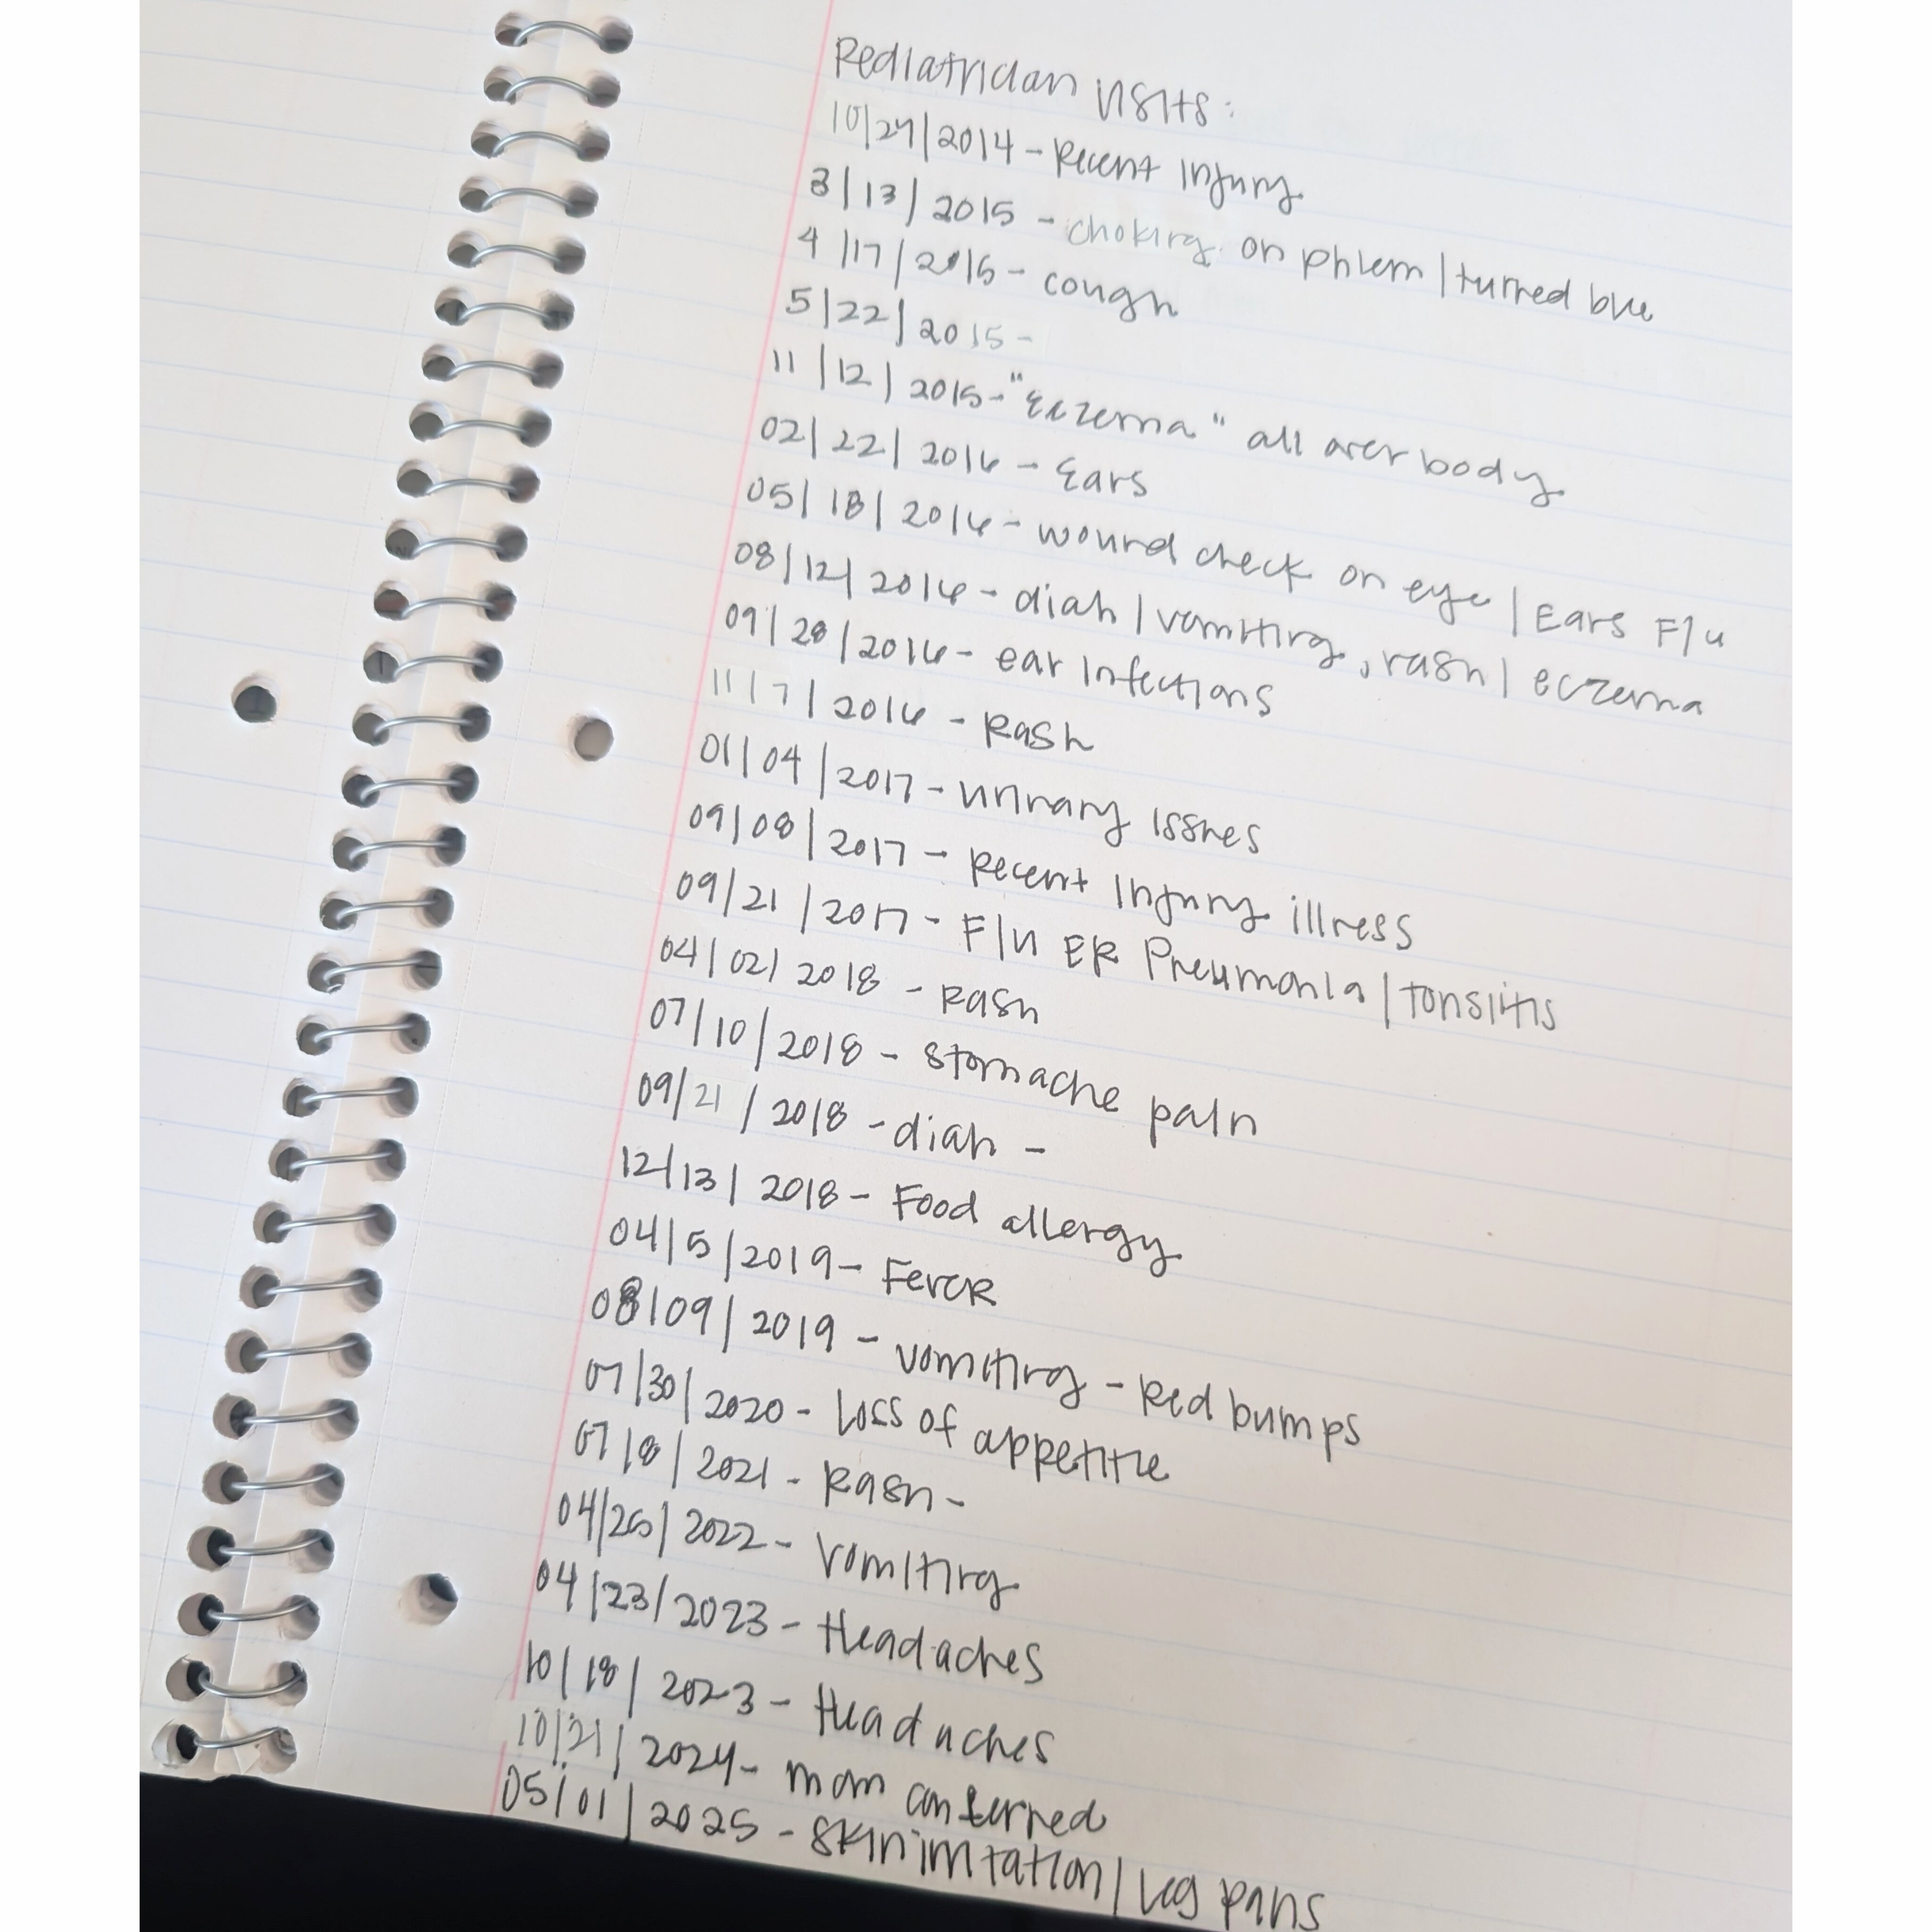

My name is Kortney and I am a single mother of two. The past couple years have been really hard on myself and my kids. With my medical issues, doing it all alone, and other unfortunate life events. But after a VERY VERY long wait to see a REAL Rheumatologist we finally saw him, and our appointment was 4 hours long unpacking the history of Brookelynn, my 11 year old daughter. One positive, was that she didn't have Lupus. But she is now known as "unicorn", a "zebra with polka dots" to this Rheumatologist. My mama heart is broken. As of right now Brookelynn has three rare conditions. One of them is so rare that as of 2024 only 100 cases were diagnosed. This condition is called Muckle Wells Syndrome. The other is a Periodic Fever Syndrome, Familial Mediterranean Fever. We also found out that she has a condition in her foot, Freibergs Infraction. She recently started an injection of antibodies that she will need either weekly, biweekly or monthly. These injections cost $19.000 each. Thankfully as of right now I do not have a cost for those but will once insurance gets involved. With these conditions, Brooke has good and bad days. One day she will be fine, the next she could have her whole body in fight mode for no reason with 106 fever, random stomach pains that will land her in he hospital, back pain so severe she screams in pain, joint pain daily, headaches, skin reactions, playing sports has been her favorite thing and as of right now it's not something she can do because the foot condition can cause pain with walking. Getting to the bottom of her medical issues has taken 11 years as this started when she was a baby. Muckle Wells is not curable, its something she will deal with for the rest of her life and it can cause hearing loss which is devastating. As much as I am thankful to finally have answers, I'm scared.

I am employed with a full time job, as well as 2 part time jobs and work as much as possible to take care of her medications, medical appts, bills, my pets, etc. Although I am working these jobs I'm also missing a lot of work for all of her specialist visits, unpaid. Which has put me in a place of almost losing my job. She does have insurance but the coverage is limited. The constant labs, office visits, tests, medications, etc have me drowning as a single mom.